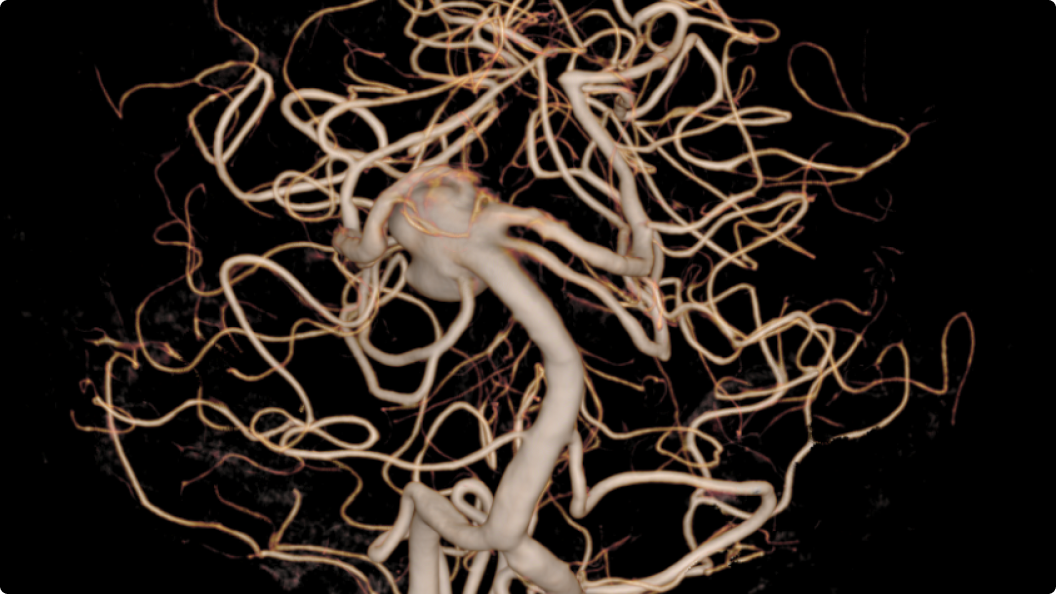

Gehirn

Intracranial aneurysms: clinical value of 3D digital subtraction angiography in the therapeutic decision and endovascular treatment.

Anxionnat et al., Radiology, 2001